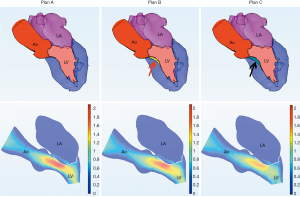

Of the 21 patients who were transferred to mitral replacement, there was one with Barlow disease (BD). The MV leaflets were redundant, with prolapse of P2 and P3. 3D-TEE showed billowing of both AML and PML, especially the P3 segment. Color Doppler showed severe MR originating from the PML. One challenge of repairing BD mitral valves is the development of postoperative SAM of the AML, which is often associated with a tall PML. As the height of the PML increases, the coaptation point gets closer to the base of the AML, and the length of the AML beyond the coaptation point (residual length) increases. Residual AML is free to move in response to the drag created by the jet flow, which can cause SAM and LVOT obstruction. We simulated the procedure with different PML lengths from 14.0 to 19.0 mm (with an 0.5 mm increase on each attempt). The residual length of the AML ranged from 2.8 to 5.4 mm (Table 5). The results show that SAM and LVOT obstruction occurred when the PML length reached 16.5 mm, with a residual length of the AML at 4.2 mm (Figure 8). The pressure gradient at the LVOT reached 17.2 mmHg after repair, but was only 6.8 mmHg before surgery.

Complications following MV repair, such as LVOT obstruction, are another consideration for surgeons in their selection of procedure. Risk factors for LVOT obstruction include a tall PML (>1.5 cm), a ratio of AML to PML length >1.3, distance between the IVS and coaptation point (LVOT height) <2.5 cm, increased basal IVS thickness >1.5 cm, and small LV cavity (LV end-diastolic dimension <4.5 cm) (23,24). However, these standards are not absolute or applicable to every patient. In our study, we discussed 2 special cases of potential LVOT obstruction. One was a patient with BD, the other had a small heart cavity. LVOT obstruction occurred when the PML length was >16.5 mm in the BD patient, and when IVS thickness was >12.0 mm in the patient with a small heart cavity. This demonstrated the great potential and advantages of 3DP modeling and CFD in individualized diagnosis and treatment.